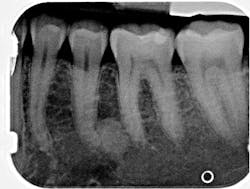

A healthy 41-year-old female presented to the office for a routine exam and checkup. Her health history was normal, and she reported no major concerns or issues.

Radiographic examination revealed a large, radiopaque mass just distal to the apical third of tooth no. 20. The area was not tender to palpation, and the tooth tested vital and WNL.

Periapical idiopathic osteosclerosis

The lack of radiolucent border and the unknown etiology of the lesion strongly indicate that this lesion is periapical idiopathic osteosclerosis. Since there are no previous radiographs to reference, this diagnosis is not concrete. This diagnosis presents no clinical significance; hence, the patient will be reexamined periodically. Any changes and subsequent treatment will be rendered.